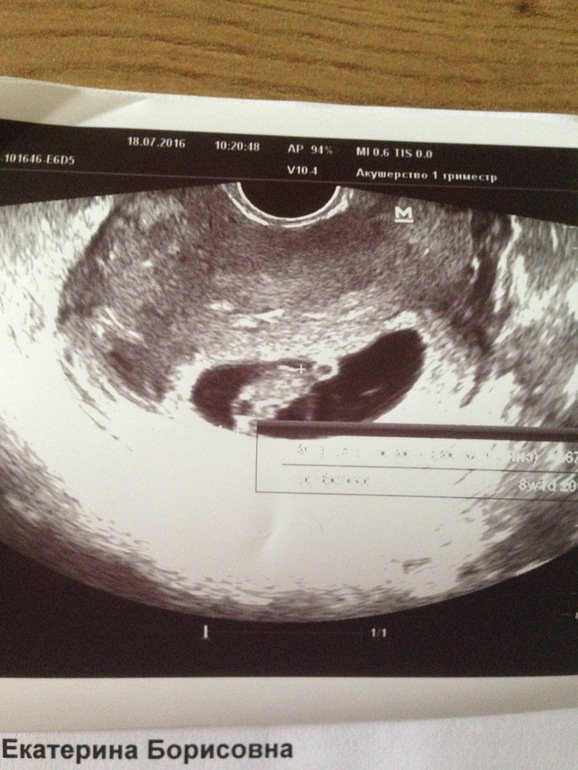

Сегодня были уже 2 раз на узи, первый раз в 6.5, а сегодня пошла только из-за того, что уезжаем в среду почти на месяц, мне хотелось быть уверенной, что с малышом все хорошо и нет угрозы. С малышом все ттттт хорошо уже КТР уже 17мм сердечко 162 удара. Почти 2 недели назад был всего 4.8 мм и сердечко 120 ударов. Растём мой пупсик тттт хорошо.

Добавлю фото малыша и пузика под кат